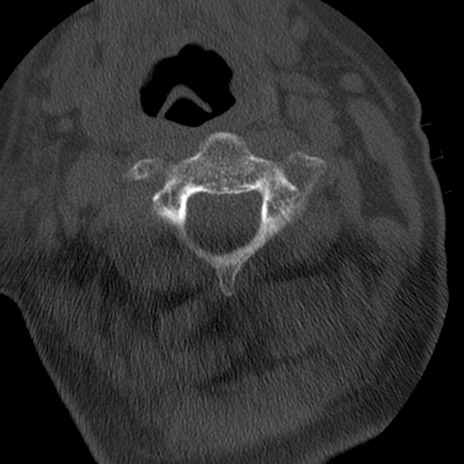

症例50 頚椎CT(横断像)

冠状断像